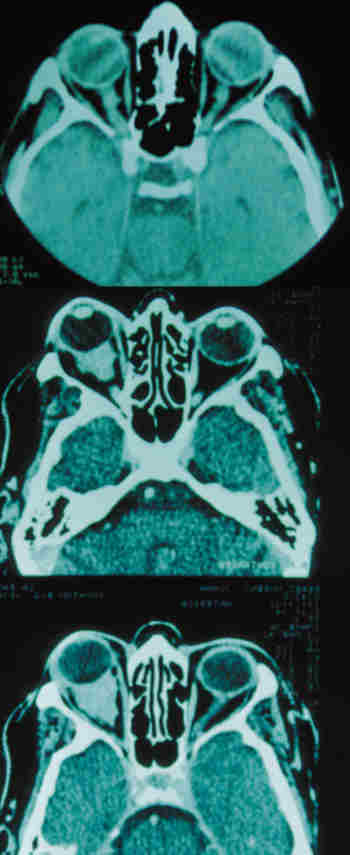

Por otra parte en los estudios de neuroimagen, los mucoceles y las sinusitis

son la causa más frecuente de proptosis unilateral en Radiología (24,25).